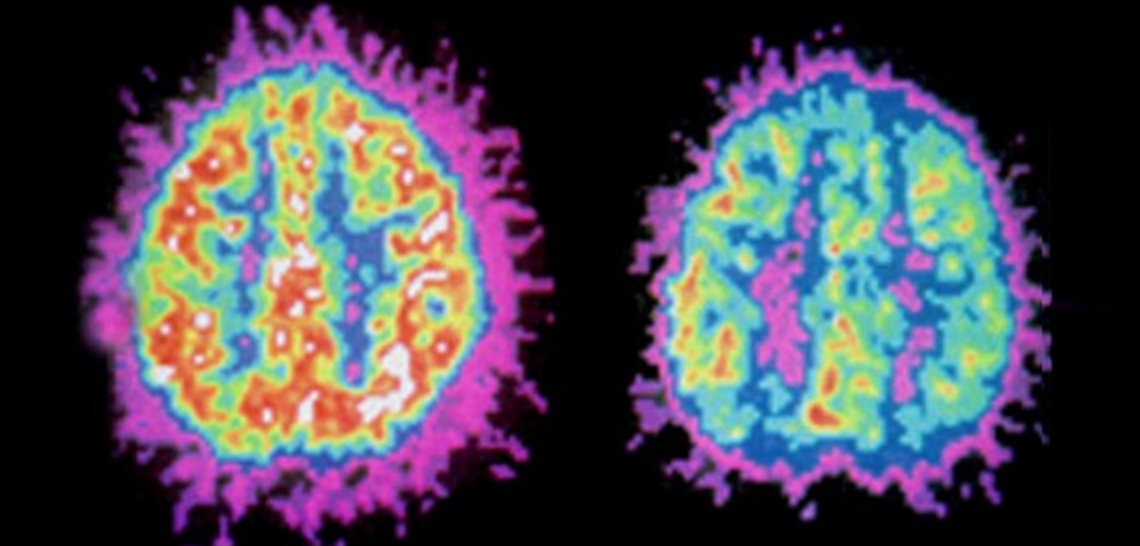

Put simply, the prefrontal cortex is like the planner and regulator, while the striatum is like the motivator and reward-seeker. When their communication is off balance, it can contribute to the challenges seen in ADHD. A PET scan can illustrate the difference between a brain with ADHD (left) and one without (right).